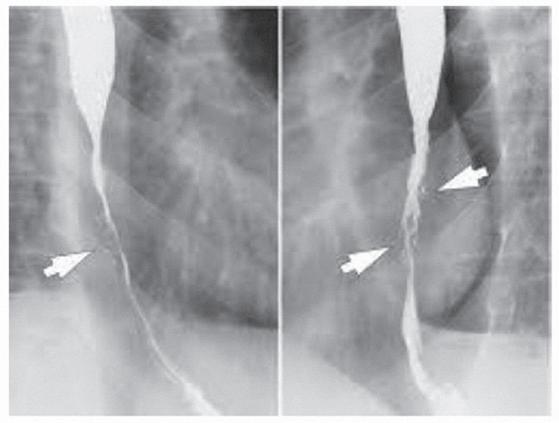

2.6.5.3 Bestraling van de slokdarm

Acute bijwerkingen

Een ontsteking van de binnenbekleding van de slokdarm (oesophagus) is de meest voorkomende bijwerking. Ze uit zich in de laatste twee weken van de behandeling tot vier weken na

Hoofdstuk 5 Behandelingsmodaliteiten

het beëindigen van de bestraling. Ze heeft een cumulatief karakter, is zelflimiterend en interfereert niet met de behandeling. Aangepaste voeding, medicatie en een antischimmelbehandeling worden opgestart.

Figuur 25 Vernauwing oesophagus

Laattijdige nevenwerkingen

Die ontstaan meer dan drie maanden na bestraling (soms tot 1 jaar) en hebben meestal een irreversibel karakter. Een chirurgische behandeling is soms aangewezen.